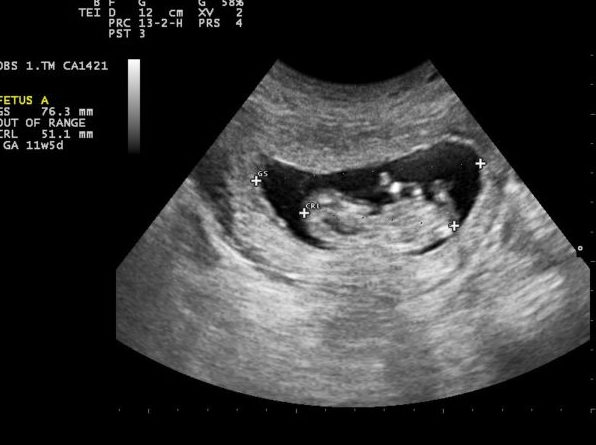

Khi bác sĩ chỉ định mẹ thực hiện phương pháp siêu âm đầu dò qua ngõ âm đạo, có thể nhận thấy túi thai với đường kính khoảng từ 2 - 3 mm xuất hiện từ ngày thứ 17 sau khi thụ tinh. Trường hợp siêu âm bụng sẽ thấy túi thai muộn hơn. Do sự phát triển của mỗi thai nhi không giống nhau do đó mẹ không nên quá lo lắng khi chưa phát hiện túi thai ở thời điểm này khi siêu âm. Mẹ hãy kiên nhẫn đợi khoảng 5 - 6 tuần sẽ thấy túi thai một cách rõ ràng nhất.

Vậy, thai mấy tuần thì siêu âm thấy túi thai? Thông thường, từ tuần thứ 8, thai nhi đã vào tổ được khoảng 2 tháng tính từ thời điểm thụ thai nên mốc khám thai định kỳ sớm nhất sẽ bắt đầu từ tuần thứ 8. Khi đó bác sĩ sẽ chỉ định mẹ bầu xét nghiệm máu, xét nghiệm nước tiểu và bắt đầu siêu âm để kiểm tra, theo dõi sức khỏe thai kỳ.

Siêu âm sẽ nhìn thấy hình ảnh túi thai khi thai kỳ ở tuần thứ 5, lúc này nồng độ HCG đạt tới 1.100. Trường hợp siêu âm không thấy túi thai có thể do thời điểm siêu âm sớm hơn mốc thời gian quy định.